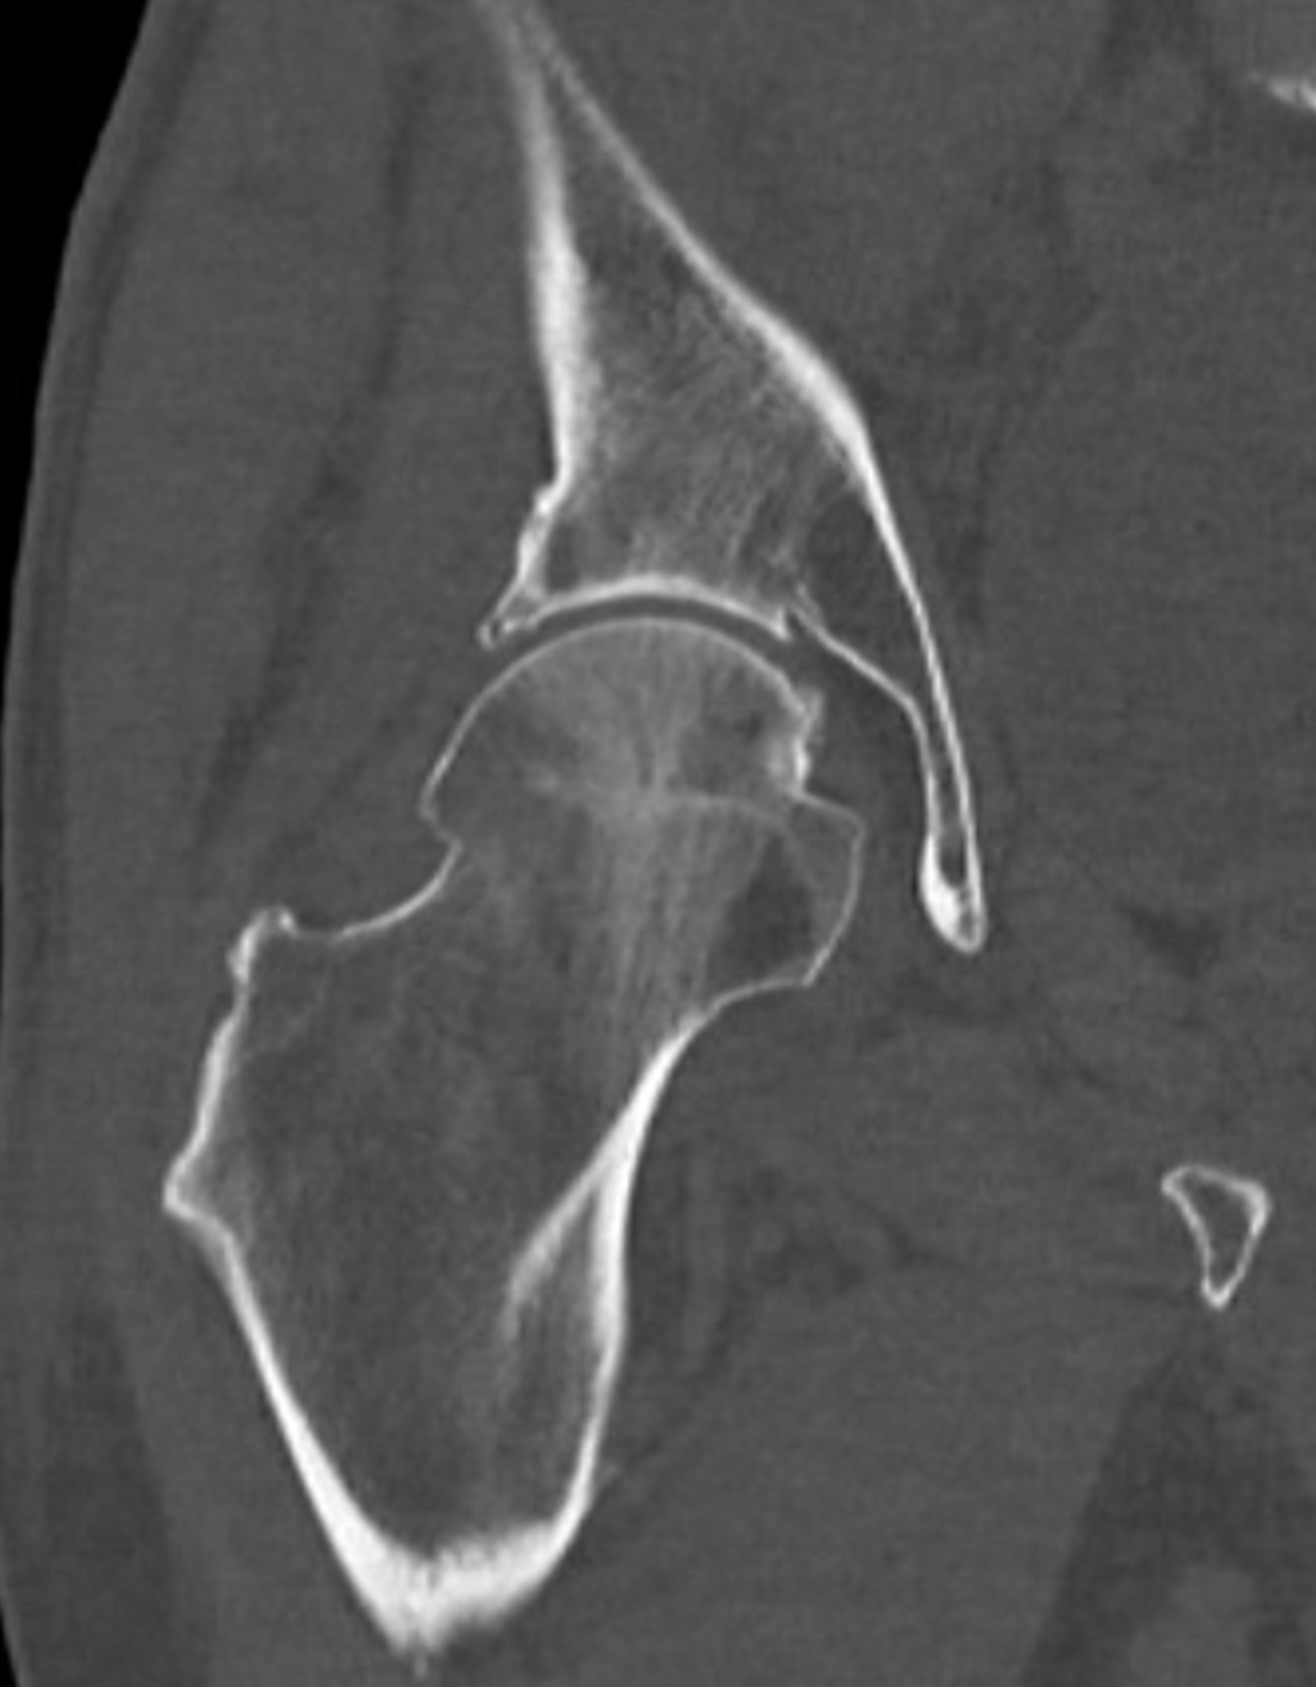

図4 右股関節 軸位像

RevolutionApexElite_Uonuma206.jpg

図5 骨条件